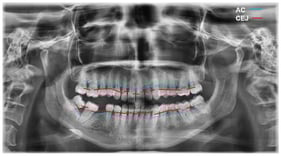

Objectives: The present study evaluated the efficacy of a preparation based on bacterial lysates of Streptococcus oralis, Aggregatibacter actinomycetemcomitans and Fusobacterium nucleatum in the treatment of experimental periodontitis in rats, compared to metronidazole. Methods: Twenty female Wistar rats were used, divided into three groups: control, bacterial lysates and metronidazole, administered for 10 days by oral lavage/gavage. Periodontitis was induced by ligatures contaminated with bacterial suspensions (109 CFU/mL) for 4 weeks. Lysates were obtained by culturing bacterial strains, centrifugation, washing, heat inactivation, ultrasonication and filtration. The evaluations included biocompatibility on HGF-1 fibroblasts, microbiological stability, clinical parameters, hematological, biochemical and histopathological analyses. Results: The lysates demonstrated the absence of cytotoxicity (cell viability 90–100%) and significant antimicrobial effect at the optimal concentration (2 × 109 CFU/mL equivalent). Both treatments significantly reduced periodontal inflammation, with no statistical differences between them. Systemic immunoinflammatory indices (SII, SIRI, AISI) increased comparably, demonstrating controlled immune mobilization, and ALT was maintained within physiological limits. Histopathological examination revealed a reduction in inflammatory infiltrate, connective tissue reorganization and bone regeneration in both treated groups. Conclusions: Bacterial lysates represent a viable therapeutic alternative with comparable efficacy to metronidazole, favorable safety profile and immunomodulatory potential in the treatment of periodontitis.